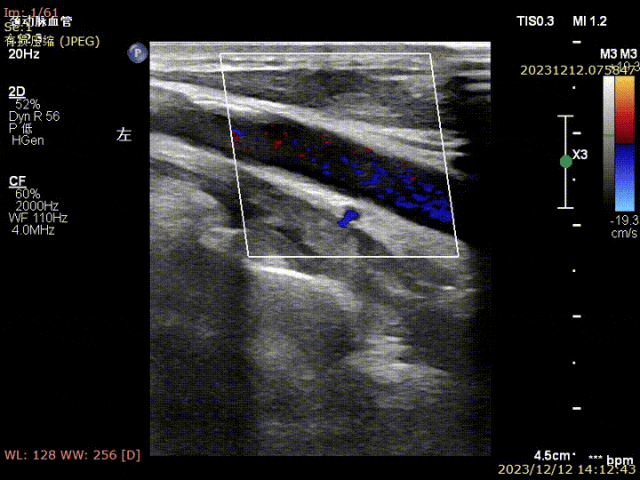

姜坤主任接诊后做彩超发现患者左侧颈总动脉分叉处硬化斑块钙化严重,颈内动脉起始部重度狭窄(狭窄程度>90%),且斑块为易损斑块。

▲患者术前颈部血管超声可见颈动脉斑块,狭窄局部血流速度明显减慢